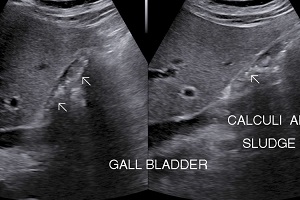

• Multiple Calculi